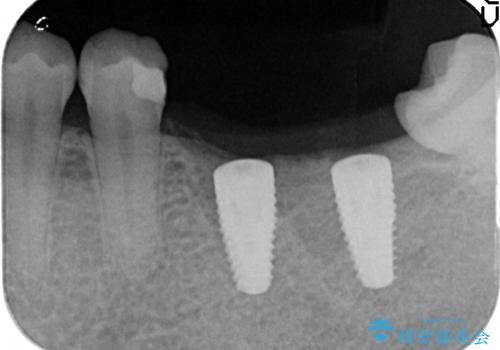

- 数年前に左下の奥歯を2本失ってから物が咬めないため何とかして欲しいと当院にいらっしゃった方の症例です。

左下にインプラント(ストローマン)を2本埋入し、オールセラミッククラウンによる補綴を行いました。

当院では主にストローマンという種類のインプラントを治療に用いています。

ストローマンは世界的にもNo1のシェアを誇り、骨との適合にも優れたインプラントです。